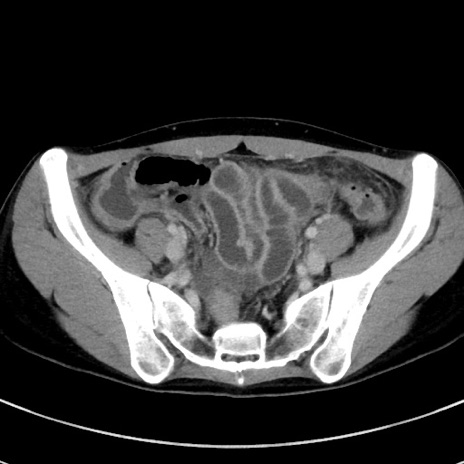

症例17(横断像)

【症例】20歳代女性

【主訴】嘔吐、下腹部痛

【現病歴】昨日夕食後に嘔吐し下腹部痛が出現。本日になっても嘔吐持続し改善しないため来院。

【身体所見】意識清明、BT 37.2℃、BP 108/67mmHg、腹部:平坦、やや硬、下腹部正中から右にかけて圧痛あり、反跳痛軽度あり、tapping pain(+)。

【データ】WBC 13600、CRP 14.94